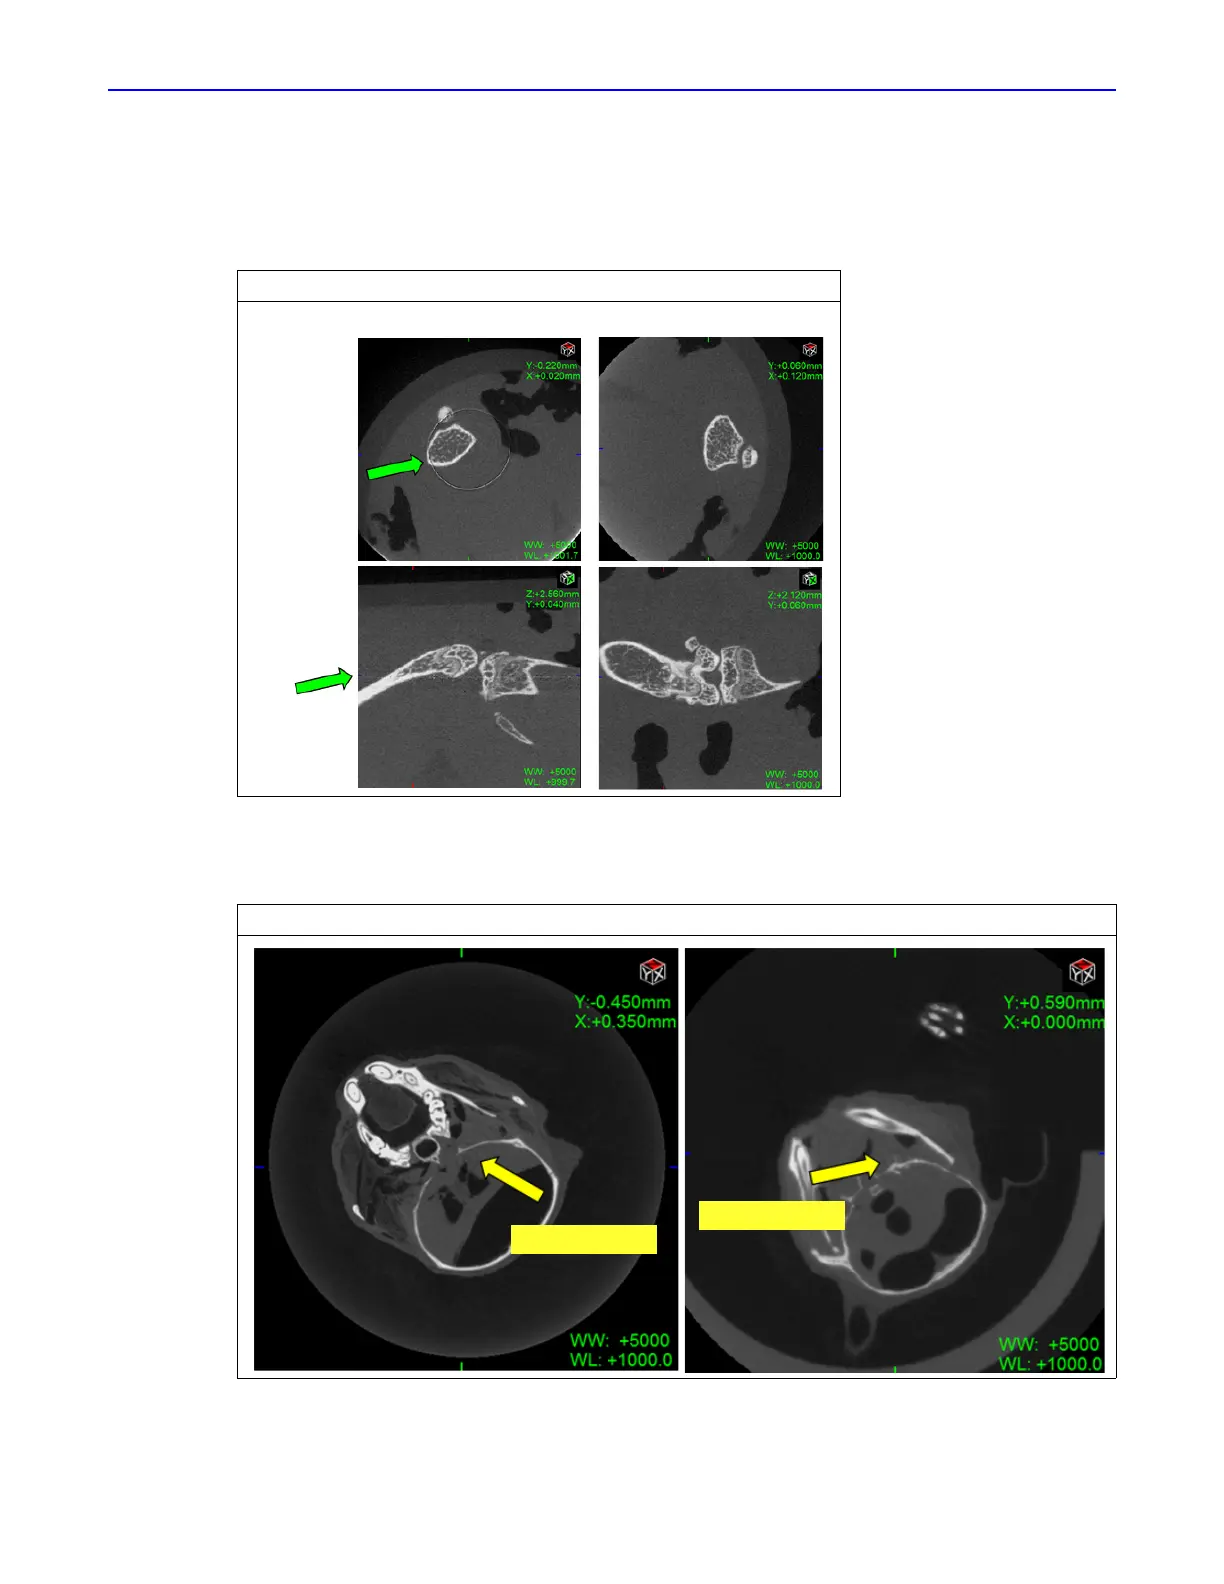

The ring reduction algorithm helps reduce image artifacts and is turned on by default. Figure 6.32

shows example images of before and after ring reduction.

Sometimes ring reduction may result in image artifacts (Figure 6.33). The artifacts are usually minor.

However, if they are unacceptable, you can turn off ring reduction and repeat the acquisition.

Figure 6.32 Images With Example Ring Artifacts

Figure 6.33 Example Image Artifacts Resulting From Ring Reduction

Before Ring Reduction After Ring Reduction

Ring

artifact

Ring

artifact

Ring artifact

Ring artifact